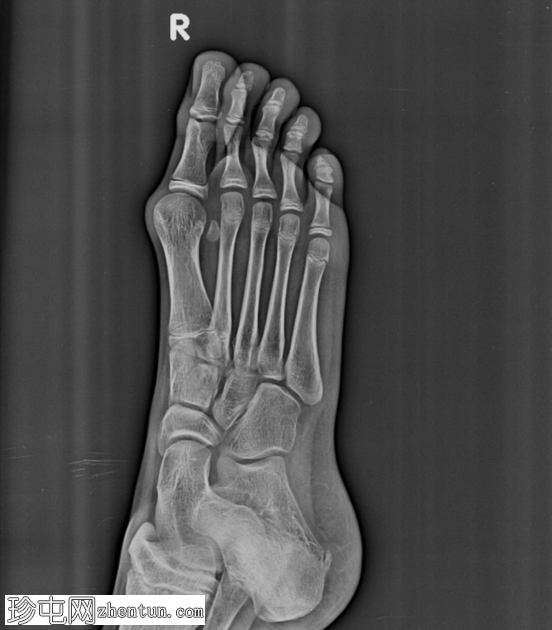

斜位片

第一跖趾关节处拇趾(拇趾)向外侧偏斜。第一跖骨向内侧偏斜,导致拇外翻角增大。近节趾骨相对于第一跖骨头轻度向外侧半脱位。第一跖骨头内侧隆起,呈圆形。

未见急性骨折或脱位。其余可见的跖骨和趾骨排列正常。未见骨侵蚀或局灶性破坏性病变。